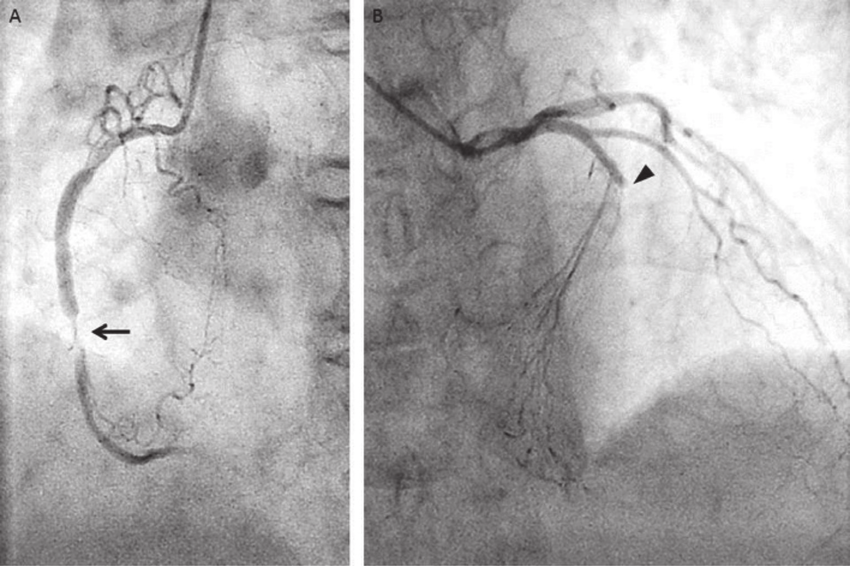

The extended model incorporates a few additional terms which account for spatial variations in the arterial radius, making it more suitable for modeling cases involving stenotic arteries. This added complexity allows the model to accurately handle flow behavior and pressure variations in the presence of arterial narrowing (stenosis) as shown in Figure 1, where changes in the geometry can significantly impact blood flow dynamics.

Although the existing model offers computational efficiency and simplicity, its limitations, such as the assumptions of cylindrical vessel geometry and uniform flow distribution, hinder its applicability in modeling stenosed arteries and other complex vascular conditions. To address these limitations, we propose an extended reduced model for studying blood flow in an artery with a variable radius. This modification is motivated by the necessity in the case of analyzing blood flow through stenosis regions formed by atherosclerotic plaque or other substances (vascular plasticity) within the walls of arteries, where the artery’s radius varies along the longitudinal direction, as illustrated in Figure 2. Unlike the well-established model introduced in [1; 3; 7], we make adjustments to the model that depend on both the artery’s radius and its derivative. Furthermore, we propose a method to extract radial velocity information from our results during the post-processing phase, allowing us to derive velocity data from the model.